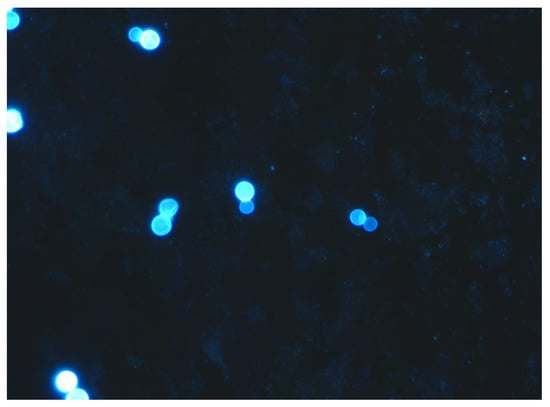

4.2. Histopathology and Cytology